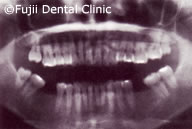

| 初診時口腔内写真およびインプラント埋入後パノラマ写真 |

ヘビースモーカーであったために、禁煙してもらい、歯のクリーニングやブラッシング指導後、およそ2年間かけて左上犬歯と左下第一小臼歯以外すべての歯を抜歯し、インプラントの埋入手術を行いました。左右上顎臼歯部はサイナスリフトなどを併用し、インプラントによる咬合の再構築を試みました。

左上第二小臼歯破折による痛みがあり来院されましたが、下顎左右の大臼歯の欠損により、後方の歯が手前に傾斜、上顎大臼歯の挺出、噛み合わせのバランスが崩れてしまっていました。下顎大臼歯にインプラントを埋入することにより咬合は回復しました。挺出した上顎大臼歯は、クラウンをかぶせましたが、歯が欠損した時点ですぐ治療をしていれば、上の歯の治療は行わず最小限の治療にとどめられたでしょう。